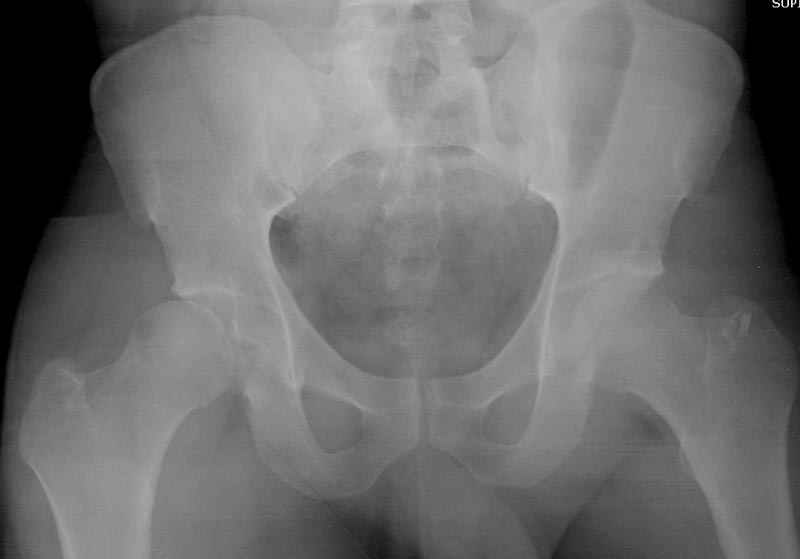

5:24 Рентгенограмма таза, вызывают врача ортопеда (снимок N1), его диагноз: закрытый переломо-вывих правого тазабедренного сустава, получает добро на закрытую репозицию в приемном отделении

5:38 Дважды неудачная попытка закрытой репозиции в приемном отделении

N 2

6:20 ответстенный врач принимает решение о репозиции в условиях операционной, предупреждаются родственники и больной, что при неудачной закрытой репозиции, о возможности открытой репозиции и фиксации задней стенки вертлужной впадины.